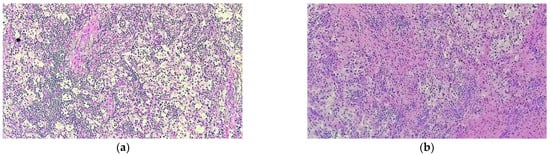

The specimen samples were fixated with 10% buffered formalin and were processed by conventional histopathological methods using paraffin embedding, sectioning and hematoxylin–eosin (HE) staining. Microscopic examination showed a diffuse infiltrate of small lymphocytes, plasma cells and frequent foamy histiocytes as well as pigment laden macrophages (siderophages) displayed around small vascular structures with slightly thickened vascular walls (Figure 7). Some histiocytes displayed abundant, pale cytoplasm with phagocytized lymphocytes, suggestive for emperipolesis. This inflammatory infiltrate extended into the adjacent bone and soft tissue (Figure 8). The inflammatory reaction includes rare fragments of devitalized bone lamellae with dystrophic calcifications, found on the periphery of the analyzed specimens.

In order to help establish an accurate final diagnosis, IHC tests were performed. To begin with, the paraffin blocks were cut and the resulting 3-μm thick sections were mounted on slides covered with poly-L-lysine. Afterwards, the sections were deparaffinized in successive toluene and alcohol baths, rehydrated (three successive alcohol baths with decreasing concentration: 96%, 80% and 70%) followed by a final bath with distilled water for 10 min. For IHC staining, we used an indirect tristadial Avidin–Biotin complex method (deparaffinization in toluene and alcohol series), rehydration, washing in phosphate-buffered saline (PBS), incubation with normal serum, for 20 min, incubation with primary antibody overnight, DAKO Labeled Streptavidin–Biotin (LSAB) kit, washing in carbonate buffer and development in 3,3′-diaminobenzidine (DAB) hydrochloride/hydrogen peroxide nuclear counterstaining with Mayer’s Hematoxylin. Immunohistochemical analysis demonstrated that the foamy histiocytes stain intensely for S100, CD68, CD163 and Cyclin D1, while CD1a reaction was negative (Figure 9).

In conclusion, the microscopic aspects corroborated with the immunohistochemical expression pattern are highly suggestive for Rosai–Dorfman Disease.

Figure 7. Prominent population of histiocytes characterized by large, round nuclei and voluminous cytoplasm showing emperipolesis with engulfment of lymphocytes (a) HE staining; 40×; (b) HE staining 400×.

Figure 8. Rosai–Dorfman disease showing (a) a prominent histiocytic infiltrate in a background of inflammatory cells, predominantly comprised of lymphocytes and plasma cells (HE staining 40×); (b) lesional histiocytes associated with fibrosis and prominent inflammatory infiltrate extended into adjacent bone and soft tissue (HE staining, 40×).